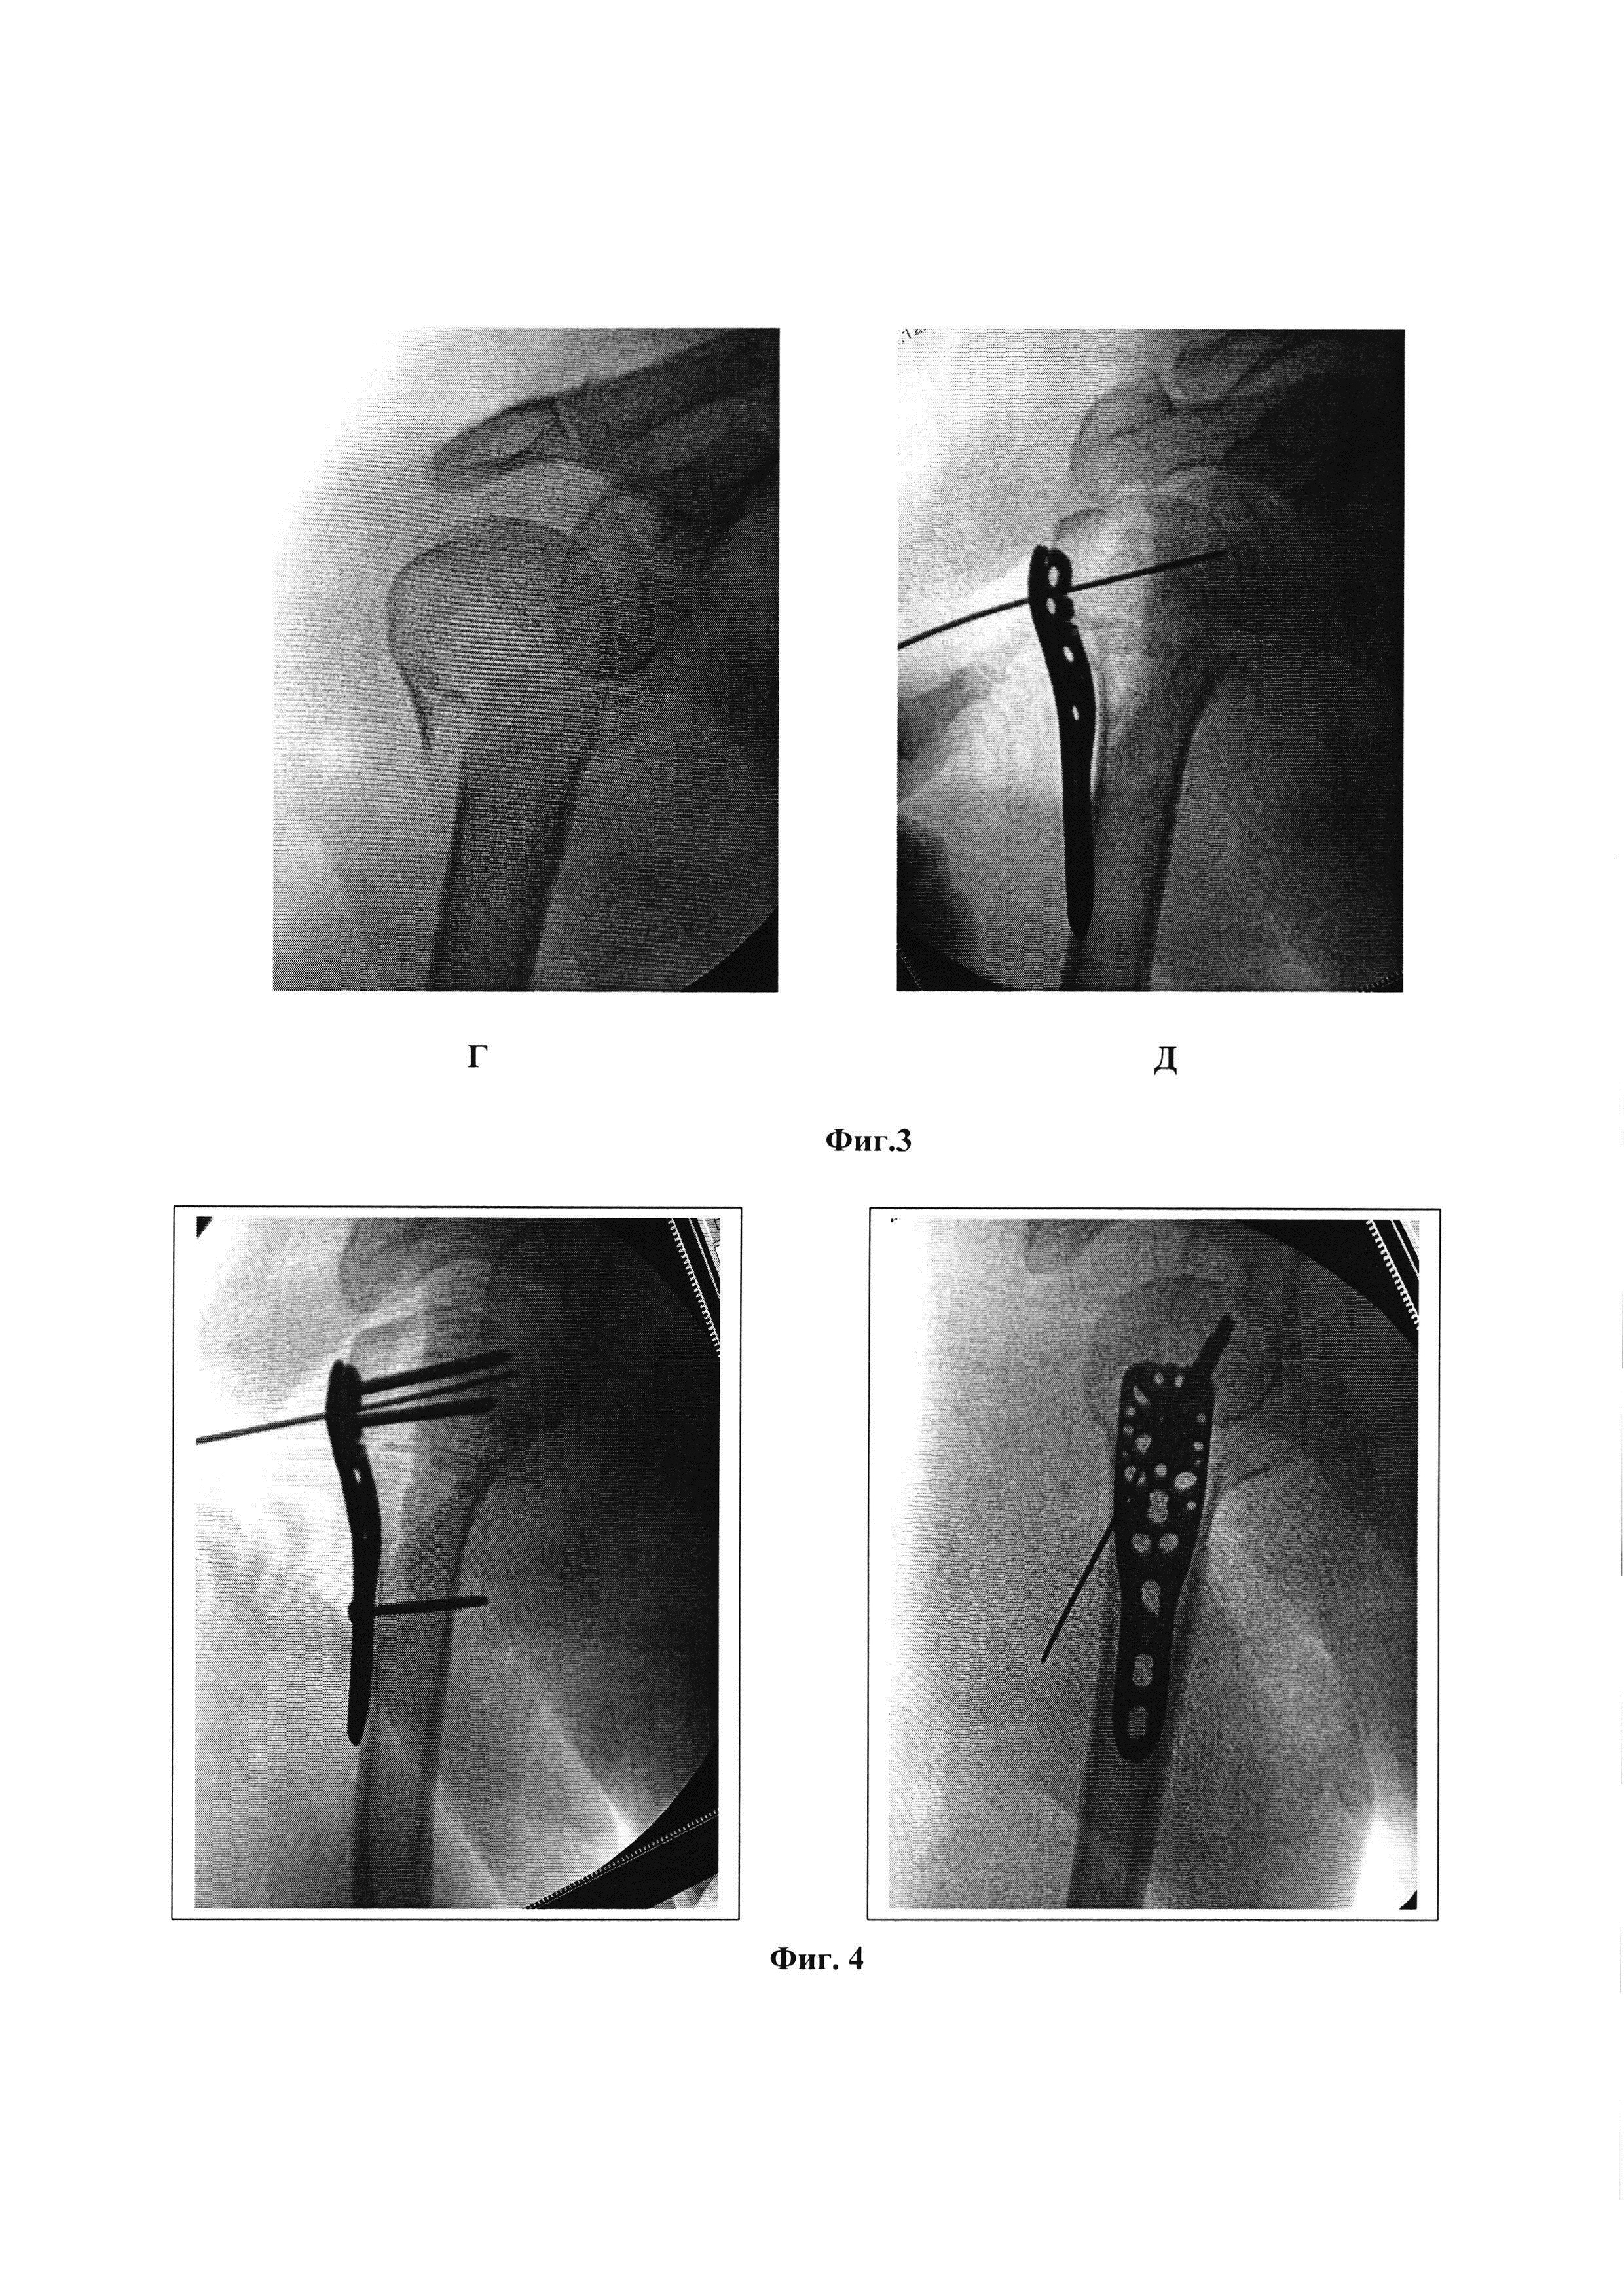

Область техники, к которой относится изобретение Изобретение относится к области медицины, а именно к травматологии, и может быть использовано для репозиции отломков при переломах проксимального отдела плечевой кости. Уровень техники Переломы проксимального отдела плечевой кости составляют около 5-7% от всех переломов у взрослых пациентов и занимают третье место по частоте среди переломов у пожилых пациентов после переломов проксимального отдела бедренной кости и дистального отдела лучевой кости. Переломы проксимального отдела плечевой кости составляют до 75% всех переломов плечевой кости у пациентов старше 60 лет, при этом у женщин они встречаются в 2-3 раза чаще, чем у мужчин [Ломтатидзе Е.Ш., Ломтатидзе В.Е., Поцелуйко С.В. [и др.] Анализ функциональных результатов внутреннего остеосинтеза при переломах проксимального отдела плечевой кости // Вестник травматологии и ортопедии им. Н.Н. Приорова. - 2003. - №3. - С. 62-66.]. Переломы данной локализации оказывают сильное влияние на функцию конечности в ближайшем и отдаленном периодах после травмы. Эпидемиологические исследования говорят о постоянном увеличении числа таких переломов и об удвоении их количества у пациентов в возрасте старше 80 лет в ближайшие 20 лет [Palvanen М., Kannus P., Niemi S., Parkkari J. Update in the epidemiology of proximal humeral fractures. Clin Orthop Relat Res 2006;442:87-92.; Song J.Q., Deng X.F., Wang Y.M., Wang X.B., Li X., Yu B. Operative vs. nonoperative treatment for comminuted proximal humeral fractures in elderly patients: a current metaanalysis. Acta Orthop Traumatol Turc. 2015;49(4):345-53.]. В настоящее время нет однозначных рекомендаций по выбору тактики лечения больных с переломами проксимального отдела плечевой кости. Это связано с большим количеством возможных вариантов лечения: консервативных и оперативных, большого количества модификаций оперативного метода лечения. Важную роль играет время, прошедшее с момента травмы до момента оперативного лечения. Задержка в проведении оперативного лечения более чем на 5 дней приводит к значительному увеличению количества осложнений таких, как аваскулярный некроз головки и вторичное смещение отломков. В случаях с раскалыванием головки плечевой кости и переломов в сочетании с вывихом анатомическая репозиция должна быть выполнена не позднее 48 часов после травмы, это снижает риск аваскулярного некроза головки плечевой кости [ При 3-х и 4-хфрагментарных переломах проксимального отдела плечевой кости неточная репозиция отломков плечевой кости (в частности большого бугорка), высокое стояние пластины и неплотное ее прилегание к кости, а также несостоятельность фиксации в послеоперационном периоде, приводит к развитию субакромиального импинджмента и плохим функциональным результатам лечения. Достижение одновременно правильного положения отломков, правильного позиционирования пластины и плотного ее прилегания к кости является сложной хирургической задачей. В настоящее время существует много способов фиксации отломков при переломах проксимального отдела плечевой кости, однако нет определенного алгоритма действий, который позволил бы добиться четкой анатомической репозиции при любом типе перелома, включая 3-х и 4-хфрагментарные переломы. Наиболее часто для репозиции отломков головки плечевой кости используют спицы в качестве джойстиков для репозиции отломков [Bucholz, Robert W.; Heckman, James D.; Court-Brown, Charles M.; Tornetta, Paul. «Rockwood And Green's Fractures In Adults, 7th Edition». Lippincott Williams & Wilkins. 2010. 1072-1075.]. Недостатком данного метода является сложность позиционирования спиц по причине смещения отломков головки плечевой кости под акромиальный отросток лопатки. Акромиальный отросток лопатки часто ограничивает амплитуду движения спиц-джойстиков, это приводит к необходимости проводить спицы несколько раз, что в свою очередь наносит дополнительную травму кости и окружающим мягким тканям. Кроме того, при проведении интенсивных манипуляций с отломками головки плечевой кости посредством спиц-джойстиков часто происходит их вырывание. Это особенно часто проявляется у пожилых пациентов со сниженной плотностью кости. Каждое вырывание спицы приводит к потере репозиции и требует повторного заведения джойстика. Потеря фиксации спицы-джойстика в кости (при ее вырывании) приводит к формированию костной полости в месте ее установки. Кроме того, частое перепроведение спиц-джойстиков приводит к дополнительной травме кости и окружающих мягких тканей, увеличению количества полостей в кости, уменьшению суммарной костной плотности головки плечевой кости (что особенно ощутимо при проведении остеосинтеза в условиях остеопороза или остеопении). Создание дополнительных костных полостей после спиц-джойстиков приводит к сложности окончательной фиксации перелома с помощью пластин, так как уменьшает фиксационные возможности винтов. Прошивание сухожилий мышц вращающей манжеты плеча (ВМП) рекомендуется многими авторами, как для репозиции, так и для усиления фиксации перелома. Однако рекомендации по тактике последовательности действий разнятся. Так Архипов С.В. и Ковалерский Г.М. прошивание сухожилий мышц вращающей манжеты плеча используют для репозиции отломка большого или малого бугорков, после чего осуществляют временную фиксацию отломков головки плечевой кости спицами Киршнера (2-3 спицы), одновременно с этим производят спицевую фиксацию проксимального отдела плеча к диафизу. После достижения временной фиксации позиционируют пластину, производят окончательную фиксацию перелома пластиной и удаляют провизорные спицы [Архипов С.В., Ковалерский Г.М. Хирургия плечевого сустава. Москва 2015 г. 171-173.]. Авторами также предлагается проведение компрессирующих винтов для достижения плотного контакта пластины с костью, а отверстия в пластине авторы используют для установки проволочных петель с целью дополнительной фиксации мелких отломков. Недостатком данного способа является предварительная фиксация отломков спицами (2-3 иногда и более). Проведение провизорных фиксирующих спиц в дальнейшем создает помехи для уложения и позиционирования пластины. Проведенные провизорные спицы часто проходят через зону максимальной костной массы отломка. Пластину приходится укладывать в обход спиц, это приводит к тому, что блокируемые винты, проходящие через пластину и фиксирующие отломки, идут через зону меньшей косной массы отломка. Перепроведение же спиц приводит к потере временной репозиции и к смещению отломков. Подшивание к пластине сухожилий только подостной и надостной мышц, без обязательного прошивания подлопаточной мышцы создают дисбаланс в плотности прилегания пластины к кости. Из уровня техники для фиксации переломов проксимального отдела плечевой кости известно использование пластин с прошиванием сухожилий мышц ВМП для репозиции отломков бугорков. При этом вначале проводят прошивание сухожилий, потом нити продевают через пластину, производят репозицию и фиксацию пластины к кости [Nho S.J., Brophy R.H., Barker J.U., Cornell C.N., & Macgillivray J.D. Innovations in the management of displaced proximal humerus fractures. The Journal of the American Academy of Orthopaedic Surgeons, 15 1 (2007), 12-26.]. Однако, прошивание сухожилий ВМП нитями только при наличии перелома в точке фиксации создает дисбаланс сил при натяжении этих нитей (то есть при репозиции отломков), что усложняет процесс позиционирования пластины. К этому же приводит и отсутствие центральной спицы, которая центрирует пластину и тем самым осуществляет плотное прижатие (правильно позиционированной) пластины к кости. Основная проблема, с которой встречается хирург при репозиции отломков и позиционировании пластины, это сложность достижения правильной и минимально травматичной репозиции отломков без помех для укладки пластины. Из уровня техники известно использование прошивания сухожилий мышц ВМП и их подшивание к пластине для увеличения прочности фиксации. Однако прошиваются только сухожилия, крепящиеся к сломанным фрагментам (сухожилия надостной и подостной мышц при переломах большого бугорка, сухожилие подлопаточной мышцы при переломах малого бугорка). Для репозиции же авторы используют большое количество спиц Киршнера и зажимы (в частности зажим Лоумена) [Lynn A. Crosby, Robert J.Neviaser Proximal humerus fractures. Evaluation and management. Springer. 2015. 99-105.]. Применение большого количества спиц Киршнера, как уже было сказано, усложняет позиционирование пластины и проведение через нее винтов. Использование для репозиции зажимов наносит дополнительную травму окружающим мягким тканям, и имеет риск повреждения огибающих плечевую кость артерий (в частности задней огибающей) и подмышечного нерва. Наиболее близким к заявляемому решению является способ остеосинтеза при переломе проксимального отдела плечевой кости (Патент на изобретение №2673146), в котором для репозиции отломков плечевой кости используют прошивание сухожилий мышц ВМП, для фиксации - штифт. Способ согласно изобретению осуществляют следующим образом. Выполняют разрез кожи и подкожной жировой клетчатки длиной 5-6 см между передним и средним пучками дельтовидной мышцы от переднелатерального угла акромиона до проекции подмышечного нерва. Разводят дельтовидную мышцу. Прошивают отдельными нитями сухожилия надостной, подостной и подлопаточной мышц, по меньшей мере, двумя стежками каждое, причем сухожилия надостной и подостной мышц прошивают на расстоянии 1-1,5 см от мест их прикрепления к большому бугорку плечевой кости, а сухожилие подлопаточной мышцы - на расстоянии 1-1,5 см от места его прикрепления к малому бугорку плечевой кости. Репозицию отломков проводят путем тракций за концы проведенных через сухожилия нитей, при этом сначала проводят репозицию большого бугорка путем тракций в латеральном и дистальном направлениях за концы нитей, проведенных через сухожилия надостной и подостной мышц, затем ротируют головку плечевой кости путем тракций в дорсальном направлении за концы нити, проведенной через сухожилие подлопаточной мышцы. Сохраняя тягу за нити, выполняют продольный разрез длиной 1-1,5 см сухожилия надостной мышцы, через который формируют в головке плечевой кости входное отверстие для штифта. После введения штифта его фиксируют с помощью блокирующих винтов, проводимых через отверстия штифта, причем проксимальные блокирующие винты проводят через большой и малый бугорки плечевой кости, а дистальный блокирующий винт - через диафиз плечевой кости. К шляпкам винтов фиксируют с натяжением проведенные через сухожилия нити, при этом к винтам, расположенным в области большого бугорка плечевой кости, фиксируют нити, проведенные через сухожилия надостной и подостной мышц, а к винту, проведенному через малый бугорок плечевой кости, фиксируют нити, проведенные через сухожилие подлопаточной мышцы. Способ позволяет уменьшить травматичность и длительность вмешательства, повысить надежность репозиции, предотвратить нарушение кровоснабжения головки плечевой кости. Однако для того чтобы прошить все перечисленные сухожилия, хирургу необходимо произвести достаточно широкий хирургический доступ. Хирургический доступ через дельтовидную мышцу ограничен снизу анатомическим ходом подмышечного нерва. Существующий трансдельтовидный доступ должен проходить не далее 5 см ниже акромиона, иначе существует риск повреждений ствола подмышечного нерва. Расположение подмышечного нерва ориентировочное и существуют анатомические особенности, которые могут приводить к более высокому расположению нерва. Чем шире хирургический доступ, тем выше риск повреждения подмышечного нерва. При этом в передних отделах подмышечный нерв представлен уже не в виде четкого ствола, а в виде множества ветвей, которые иннервируют переднюю порцию дельтовидной мышцы. Производя широкое разведение дельтовидной мышцы (на 5-6 см от акромиона) хирурги пересекают все мелкие, идущие к передней части дельтовидной мышцы, пучки нервов. Это приводит к денервации и атрофии передней порции дельтовидной мышцы. Чем меньше разводятся пучки дельтовидной мышцы, тем больше мелких ветвей подмышечного нерва будет сохранено. Кроме того, предложенная последовательность прошивания сухожилий надостной, подостной и подлопаточной мышц, по меньшей мере, отдельными нитями с двумя стежками каждое, является менее удобной, зачастую приводящая к применению дополнительных устройств для доступа к сухожилию надостной мышцы, т.к. после переломов, смещение отломков таково, что сухожилие надостной мышцы уходит часто глубоко под акромион и физически вытащить его от туда для прошивания без специальных приспособлений (спиц, элеваторов и т.д.) не возможно. Кроме того, способ репозиции фрагментов кости в известном решении сопряжен с высоким риском их смещения при введении импланта, в связи с тем, что после прекращения тракций за нити отломки возвращаются на место под действием силы мышц, и при введении штифта нет центра приложения сил во время тракций. При этом установка проксимальных блокирующих винтов подразумевает наличие громоздких направителей, которые мешают сохранению тракций за джойстики. Кроме того, фиксация нитей «джойстика» к шляпкам винтов также имеет свои недостатки. Шляпки винтов для блокирующего штифта имеют бочкообразный вид. При введении винтов плотно к кости, места для накидывания на головку винта нити совсем не остается. Это может приводить к соскакиванию нити со шляпки винта и ослаблению фиксации. Недовведение винта до кости для облегчения фиксации нити вокруг него может приводить к субакромиальному импинджменту (соударению шляпки винта и акромиального отростка лопатки). Помимо этого, прикрепление нитей от надостной и подостной мышц к винту фиксирующему большой бугорок (точку прикрепления этих мышц), а от сухожилия подлопаточной мышцы к винту, проведенному через малый бугорок, увеличивает вырывающую силу, приложенную к винту. Кроме того, данный вид остеосинтеза можно применять только в ранние сроки после травмы. Через 5-7 дней формирующиеся между отломками рубцы не позволят произвести точную репозицию отломков по данной методике, или потребуют дополнительных хирургических доступов. Так же дополнительную травму суставу наносит разрез надостной мышцы (1-1,5 см) для формирования канала для введения штифта. Решаемой технической проблемой является разработка технически несложного, анатомичного и малотравматичного способа остеосинтеза переломов проксимального отдела плеча, включая 3-х и 4-х фрагментарные переломы, переломы в условиях снижения костной плотности, путем остеосинтеза их пластиной, обеспечивающего адекватную репозицию отломков, их надежную фиксацию и профилактику вторичного смещения в любые сроки после травмы. Раскрытие сущности изобретения Техническим результатом, на достижение которого направлено заявленное изобретение, является обеспечение надежной фиксации отломков как при простых 2-х фрагментарных, так и при тяжелых 3-4 фрагментарых переломах проксимального отдела плечевой кости, на любых сроках после травмы, при минимизации риска развития осложнений, обусловленных оперативным вмешательством. Технический результат достигается за счет реализации способа остеосинтеза при переломе проксимального отдела плечевой кости, включающий хирургический доступ к плечевому суставу, прошивание отдельными нитями сухожилий надостной, подостной и подлопаточной мышц с последующей репозицией отломков посредством тракций за концы проведенных через сухожилия нитей, после чего проводят остеосинтез с использованием импланта с фиксацией концов нитей к импланту и фиксацией импланта к плечевой кости блокирующими винтами, при этом: - к плечевому суставу осуществляют дельтопекторальный доступ с разрезом кожи и подкожной жировой клетчатки между дельтовидной и большой грудной мышцами; - в качестве импланта используют пластину с отверстиями для проведения блокирующих винтов для остеосинтеза проксимального отдела плечевой кости; - прошивание сухожилий проводят сначала подлопаточной мышцы, затем надостной и подостной; - после прошивания сухожилий концы нитей продевают через предназначенные для проведения нитей отверстия в пластине, центрируют пластину относительно суставной поверхности плечевой кости, после чего в центральное отверстие в пластине устанавливают центральную спицу, с последующей репозицией отломков путем тракций за концы нитей, удерживая пластину с проведенной центральной спицей; - концы нитей фиксируют к отверстиям в пластине. Прошивание сухожилий подлопаточной, надостной и подостной мышц проводят нерассасывающимися нитями (Терилен 5, FiberWire 2 и др.) на расстоянии 1 см от места прикрепления сухожилия к точке фиксации (большому или малому бугорку), как показано на фиг. 1, 2. При этом каждое сухожилие прошивают нитью крестообразным швом с двукратным пересечением под прямым углом лини шва, расположенной параллельно соответствующей торцевой стороне пластины, с выводом концов нитей с внешней стороны сухожилия. Прошивание осуществляют в последовательности 1-6, указанной на фиг. 1. В способе используют предизогнутую пластину для проксимального отдела плечевой кости. Оперативный доступ производят через стандартный дельто-пекторальный доступ. Выполняют разрез кожи и подкожно-жировой клетчатки начиная от клювовидного отростка лопатки до в/3 плеча длинной 15 см., находят v.cephalica, и отводя ее латерально осуществляют доступ между дельтовидной и большой грудной мышцами к плечевому суставу. Для проведения репозиции концы нитей идущих от сухожилий продевают через отверстия в пластине, соответствующие направлению хода волокон сухожилия: нити, идущие от подлопаточной мышцы продевают через отверстия на переднем краю пластины, нити от надостной мышцы - через задне-верхние отверстия в пластине, нити от подостной мышцы - через отверстия, расположенные по заднему краю пластины. Центрируют пластину после продевание нитей через отверстия в пластине под электронно-оптическим преобразователем, ориентируясь на суставную поверхность плечевой кости так, чтобы угол между плоскостью суставной поверхности и продольной осью пластины соответствовал шеечно-диафизарному углу плечевой кости, после чего устанавливают центральную спицу, проходящую через центр пластины и центр головки плечевой кости, при этом добиваются правильного угла наклона суставной поверхности головки плечевой кости к продольной оси пластины (оптимально 130°). Репозицию отломков путем тракций за концы нитей осуществляют посредством натяжения нитей (всех 3 нитей одновременно), фиксирующих ВМП, прижимая пальцем пластину к проксимальному отделу плечевой кости. При этом сначала производится натяжение нитей и только потом, при натянутых нитях, осуществляют прижатие пластины к уже репонированным отломкам плечевой кости. Эта манипуляция позволяет добиться быстрой и качественной репозиции отломков и обеспечить плотное прилегание пластины к кости. Пластину фиксируют к проксимальному отделу плечевой кости блокируемыми винтами. Удерживают нити и плотно прижимают пластину к кости, производят рассверливание по направителю наиболее удобных для вкручивания винтов отверстий. После чего фиксируют пластину винтами. Первыми используют отверстия, находящиеся в верхне-переднем квадрате пластины, так как они просты в установке из имеющегося хирургического доступа и позволяют зафиксировать пластину изолированно к проксимальному отделу кости. Проведя проксимальные винты, фиксируют пластину к диафизу кости через овальное отверстие кортикальным винтом 3,5 мм, позиционируя передний край пластины позади сухожилия длинной головки двухглавой мышцы. Контролируют положение отломков на ЭОП. Фиксацию концов нитей к отверстиям в пластине осуществляют путем поочередного завязывание нитей. Первым фиксируют к пластине сухожилие подлопаточной мышцы. В положении внутренней ротации плеча нити завязываются на 6 узлов. Далее в положении отведения и наружной ротации плеча фиксируют так же 6-ю узлами сухожилие надостной мышцы. Последним этапом, в положении наружной ротации плеча фиксируют к пластине сухожилие подостной мышцы. Так как длина кортикального винта которым изначально фиксируется диафиз кости часто велика, то он в дальнейшем его заменяют на более короткие блокирующие винты. Кроме того, данный способ остеосинтеза осуществим на любых сроках после травмы, не требует дополнительного разреза сухожилия надостной мышцы, и производится через анатомически безопасный интервал между мышцами (дельтовидной и большой грудной), исключающий повреждение дельтовидной мышцы (как основной силы осуществляющей движения в плечевом суставе). Таким образом, в заявляемом решении в отличие от способа - прототипа, выполняют дельтопекторальный доступ, который осуществляется между дельтовидной и большой грудной мышцами, который позволяет осуществить широкий хирургический доступ к плечевому суставу, без риска послеоперационных неврологических осложнений. Прошивание первым этапом сухожилия подлопаточной мышцы и тракция за данный джойстик позволяет «вытащить» сухожилие надостной мышцы из-под акромиона и значительно более проще прошить сухожилия, не используя металлические инструменты. Репозиция отломков осуществляется одновременно с их фиксацией к пластине, тем самым нет риска их смещения при введении импланта. Наличие центральной спицы создает вектор приложения всех сил, который направлен к пластине. За счет одновременной тракций за джойстики и прижимания пластины к кости создается репозиционный момент, который способствует одновременной репозиции всех сухожилий и отломков. Фиксация отломков в пластине происходит без громоздких направителей, что облегчает сохранение натяжение нитей и сохранение репозиции отломков. Фиксация нити в отверстии в пластине (по сравнению с прототипом, где фиксация осуществляется к шляпкам винтов) является значительно более надежной, при этом отсутствует риск ослабления фиксации. Поочередное прошивание всех сухожилий мышц ВМП независимо от наличия перелома костного фрагмента в точке прикрепления позволяет реализовать репозицию отломков с помощью нерассасывающихся нитевых джойстиков. Репозиция достигается с помощью установки центральной спицы и баланса между нитевыми джойстиками. Центральная спица, а также обязательное прошивание всех трех сухожилий мышц ВМП позволяет правильно распределить силы при репозиции, при этом не смещая пластину (из-за дисбаланса нитей). Дисбаланс нитей, может развиваться, во-первых, при их наложении не за все три сухожилия. Во-вторых, даже при наложении нитей за все три сухожилия, при отсутствии центральной спицы, тракция за нити приводит к смещению пластины кверху и кзади. Попытки одновременно удержать пластину в правильном положении и соблюсти баланс между нитями приводят или к недонатяжению нитей (и возможно к недорепозиции отломков) или к нарушению положения пластины (больше кверху и кзади, что может приводить к субакромиальному импинджмент синдрому). Подтягивание сухожилия мышц ВМП к пластине (при натягивании нитевых джойстиков) позволяет поставить костный отломок большого бугорка под пластину, тем самым обеспечивая его плотное прижатие последней после выполнения окончательного остеосинтеза и в тоже время фиксацию его винтом через зону максимальной костной массы отломка. Разработанная оригинальная последовательность манипуляций позволяет добиться быстрой, точной и надежной репозиции, а также стабильной фиксации при любых типах переломов проксимального отдела плечевой кости (3-х, 4-х фрагментарных, в том числе и условиях остеопороза). При осуществлении способа обеспечивается плотная фиксация пластины к проксимальному отделу плечевой кости, что позволяет минимизировать риск осложнений, например, импинджмета пластиной, так как уменьшается зазор между пластиной и костью и пластина легко заходит в субакромиальное пространство при отведении плеча. Краткое описание чертежей Изобретение поясняется чертежами, где на фиг. 1 представлена схема прошивания подлопаточной мышцы, на фиг. 2 - схема проведения нитей через пластину, на фиг. 3 представлены этапы репозиции отломков проксимального отдела плечевой кости: А -поочередное прошивание сухожилий мышц ВМП, позиционирование пластины, установка центральной спицы, продевание нитей через соответствующие отверстия в пластине; Б, В - натяжение нитей, репозиция отломков; Г, Д - интраоперационные рентгенограммы до и после репозиции: на фиг. 4 - этапы репозиции отломков проксимального отдела плечевой кости: произведена фиксация пластины к проксимальному отделу плечевой кости блокируемыми винтами и фиксация диафиза кортикальным винтом 3,5 мм; на фиг. 5 - конечный этап операции: А, Б - рентгенологический контроль положения отломков и фиксатора; В - вид раны, фиксация нитей к пластине; на фиг. 6 - рентгенограммы, демонстрирующие клинический пример: А и Б - рентгенограммы после травмы; В - после операции; Г и Д - через 3 месяца после операции; Е и Ж - через 6 месяцев после операции, перелом сросся. Осуществление изобретения Последовательность действий по остеосинтезу при переломах проксимального отдела плечевой кости заключается в следующем. Вначале прошивают сухожилия мышц ВМП, затем нити продевают через пластину, далее устанавливают центральную спицу позволяющую центрировать натяжение нитей-джойстиков, и репонировать отломки плечевой кости. Последовательность прошивания сухожилий: вначале прошивают сухожилие подлопаточной мышцы, затем сухожилие надостной мышцы, после чего - сухожилие подостной мышцы. Данная последовательность дает возможность поэтапно достичь репозиции отломков головки плечевой кости. Первый шов проводят через наиболее доступное при переднем дельто-пекторальном доступе сухожилие подлопаточной мышцы. В дальнейшем манипуляция с первым джойстиком-держалкой позволяет достичь частичной репозиции головки плечевой кости и облегчить доступ к сухожилию надостной мышцы, которое находится глубоко в субакромиальном пространстве. Прошивание вторым этапом сухожилия надостной мышцы и манипуляция данным (вторым) джойстиком позволяет получить доступ и прошить еще более тяжело достигаемое (через передний дельтопекторальный хирургический доступ) сухожилие наружного ротатора (подостной мышцы). При использовании пластин для проксимального отдела плечевой кости их отверстия применяются для подшивания к пластине сухожилий мышц вращающей манжеты плеча. Однако данная манипуляция (по рекомендациям производителя) применяется при переломах соответствующих участков плечевой кости (точек прикрепления данных сухожилий). В изобретении предлагается прошивать все три сухожилия мышц независимо от наличия перелома соответствующего фрагмента плечевой кости, т.к. это позволяет достичь правильного баланса сил при репозиции отломков и улучшить плотность прилегания пластины к кости, тем самым увеличивая прочность фиксации перелома. Ниже представлено более детальное описание заявляемого способа. Операцию производят под проводниковой анестезией в положении больного на спине. Укладку больного выполняют эксцентрично относительно продольной оси операционного стола, смещая поврежденное плечо ближе к центру стола. Голову пациента фиксируют дополнительными упорами, электронно-оптический преобразователь располагают со стороны здорового надплечья. Оперативный доступ производят через дельто-пекторальный доступ. Выполняют разрез кожи и подкожно-жировой клетчатки начиная от клювовидного отростка лопатки до в/3 плеча длинной 15 см., находят v.cephalica, и отводя ее латерально осуществляют доступ между дельтовидной и большой грудной мышцами к плечевому суставу. После доступа к плечевой кости, поочередно идентифицируют: большую грудную мышцу, выходящее из-под нее сухожилие длинной головки двухглавой мышцы, короткую головку двухглавой мышцы. Прослеживают сухожилие длинной головки двухглавой мышцы до уровня межбугорковой борозды и идентифицируем большой и малый бугорки плечевой кости. От малого бугорка начинается сухожилие подлопаточной мышцы, которое идет под короткой головкой двухглавой мышцы. Первым этапом находят сухожилие подлопаточной мышцы и прошивают. Прошивание сухожилия подлопаточной мышцы производят нерассасывающимися нитями (например, Терилен 5, FiberWire 2) на расстоянии 1 см от малого бугорка. Далее нити берут на держалку (фиг. 1). Вторым этапом производят прошивание сухожилия надостной мышцы. Для этого идентифицируют акромиально-клювовидную связку, отводят ее вверх, после чего осуществляя тракцию за сухожилие подлопаточой мышцы, находят и выводят для прошивания из под акромиального отростка лопатки сухожилие надостной мышцы. Схема прошивания сухожилия и тип нитей одинаковы для всех сухожилий мышц вращающей манжеты плеча. Причем, чем тоньше и прочнее используемые нити, тем меньшими будут узлы после фиксации сухожилий к пластине. Третьим этапом идентифицируют и прошивают сухожилие подостной мышцы. Сухожилие мышцы крепится к середине заднего края большого бугорка. Для облегчения прошивания сухожилия подостной мышцы используют тракцию за сухожилие надостной мышцы. В результате получают три нитевых джойстика (подлопаточный, надостный и подостный). Данные джойстики позволяют в полном объеме контролировать положение отломков и головки плечевой кости без риска их прорезывания, что часто происходит со спицевыми джойстиками в условиях сниженной костной массы у пожилых людей. Следующим этапом является поочередное продевание нитей, идущих от сухожилий ВМП (вращающей манжеты плеча), через соответствующие отверстия в пластине для проксимального отдела плечевой кости (фиг. 2). Особенностью остеосинтеза 4-х фрагментарных переломов проксимального отдела плечевой кости является проведение костной пластики до использования пластины. Могут быть использованы костные аллотрансплантаты для заполнения дефекта между бугорками и отломком суставной поверхности. Далее производят позиционирование пластины, располагая ее позади межбугорковой борозды и на 5 мм ниже верхнего края большого бугорка. После чего фиксируют пластину одной центральной спицей Киршнера. Установка центральной спицы является важным моментом операции. Данная спица является опорной. Ее наличие позволяет центрированно прижимать пластину при натяжении нитей, в тоже время установка данной центральной спицы определяет вектор репозиции сломанных участков проксимального отдела плечевой кости. Прошивание же сухожилий мышц ВМП, крепящихся к несломанным фрагментам, создает компенсаторные силы, препятствующие искривлению спицы и однобокому (ацентричному) смещению пластины, что также формирует правильный вектор репозиции сломанных фрагментов. Положение пластины проверяют на ЭОП (Электронно-оптическом преобразователе), ориентируясь по расположению центральной спицы. После чего производят натяжение нитей фиксирующих ВМП, прижимая пальцем пластину к проксимальному отделу плечевой кости. Эта манипуляция позволяет добиться быстрой и качественной репозиции отломков и обеспечить плотное прилегание пластины к кости (фиг. 3 А-Д). Следующим этапом является фиксация пластины к проксимальному отделу плечевой кости блокируемыми винтами. Пластину устанавливают накостно, что не требует проведения дополнительного разреза сухожилия надостной мышцы. Удерживая нити и плотно прижимая пластину к кости, производят рассверливание по направителю наиболее удобных для вкручивания винтов отверстий. После чего фиксируют пластину винтами. Первыми следует использовать отверстия, находящиеся в верхне-переднем квадрате пластины, так как они просты в установке из имеющегося хирургического доступа и позволяют зафиксировать пластину изолированно к проксимальному отделу кости. Проведя проксимальные винты, фиксируют пластину к диафизу кости через овальное отверстие кортикальным винтом 3,5 мм, позиционируя передний край пластины позади сухожилия длинной головки двухглавой мышцы. Контролируют положение отломков на ЭОП (фиг. 4). Вкручивание диафизарного винта позволяет добиться правильной репозиции диафиза относительно проксимального отдела кости. Следующим этапом производят затягивание и фиксацию нитей к пластине, удаление центральной спицы и установка дополнительных винтов. При этом подлопаточную мышцу фиксируют через отверстия на переднем краю пластины, надостную мышцу - через задне-верхние отверстия в пластине, подостную мышцу - через отверстия расположенные по заднему краю пластины. Так как длина кортикального винта, которым изначально фиксируется диафиз кости, часто велика, то он в дальнейшем заменяется на более короткие блокирующие винты (фиг. 5). Фиксация отломков пластиной осуществляется по принципам абсолютной стабильности, что позволяет добиться прочной фиксации и начать раннюю реабилитацию. В 2017-2018 годах в отделении неотложной травматологии опорно-двигательного аппарата НИИ скорой помощи им. Н.В. Склифосовского, согласно заявляемому способу было прооперировано 32 пациента (27 женщин и 5 мужчин) старше 60 лет с переломами шейки плечевой кости. Средний возраст пострадавших 71,4 года. Таблица 1. Распределение пациентов с переломами проксимального отдела плечевой кости по полу и типу перелома. Всем больным при поступлении производили рентгенологическое исследование в 2-х проекциях, оценивали индекс кортикального слоя (ИКС) по Tingard, который определяется как среднее арифметическое толщины 4-х кортикальных слоев на стандартных прямых рентгенограммах. Для исследования были отобраны пациенты с пониженной минеральной плотностью кости, у которых ИКС был менее 4 мм. У всех пациентов причиной перелома была низкоэнергетичная травма. Оперативное лечение производили в первые 4-5 дней после травмы. Фиксацию перелома проводили блокируемыми пластинами для проксимального отдела плеча (DC или PHILOS). После проведения остеосинтеза проводили рентгенологическое исследование для оценки качества репозиции (в том числе шеечно-диафизарного угла). В послеоперационном периоде руку фиксировали косыночной повязкой на 5 недель. С 1 дня после операции назначали активную лечебную гимнастику. Количество и интенсивность упражнений увеличивали по мере уменьшения болевого синдрома. Контрольные обследование больных проводили в сроки 1,5; 3 и 6 месяцев. Оценивали жалобы пациентов (в частности интенсивность болевого синдрома), объем движений в плечевом суставе, проводили рентгенологическое исследование в 2-х проекциях и ультразвуковое исследование плечевого сустава. У всех прооперированных пациентов интраоперационно удалось добиться удовлетворительной репозиции и правильного шеечно-диафизарного угла. Оценка результатов лечения. При оценке рентгенологических данных. • Достигнутое интраоперационно положение отломков и шеечно-диафизарный угол сохранялись в течение всего срока наблюдения. • У всех прооперированных пациентов переломы срослись. При оценке данных ультразвукового исследования выявили. Оценка функциональных результатов пациентов прооперированных по вышеуказанной методике. Клинический пример. Пациентка 76 лет. 4-х фрагментарный перелом. Пациентка прооперирована по предложенной методике. Интраоперационно удалось добиться правильного положения отломков. При динамическом наблюдении за пациенткой отмечено сохранение достигнутого положения отломков и отсутствие признаков несостоятельности фиксации. Перелом сросся. Данные УЗИ коррелировали с функцией плечевого сустава. Через 6 месяцев после операции отведение и сгибание были более 170 градусов.